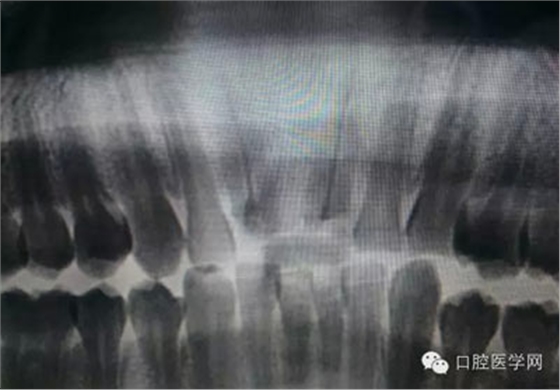

根管治療,我們?cè)诖髮W(xué)的時(shí)候就學(xué)習(xí)的東西,標(biāo)準(zhǔn)就在那里放著,可是很多時(shí)候我們熟視無睹,放任我們的想象去做。我們多些重視,多些心思,會(huì)好很多,認(rèn)真對(duì)待每顆牙齒。